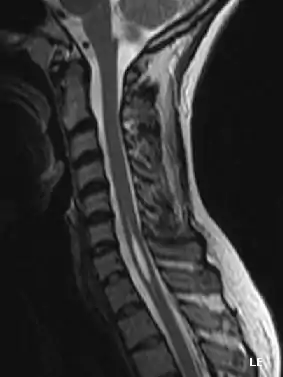

هر چند سیتی اسکن، ماهیچهنگاری برقی (الکترومیوگرافی) و نخاعنگاری myelogram همه کمککننده هستند ولی بهترین روش تشخیص با امآرآی است.